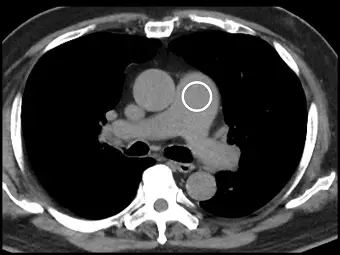

患者接受 CT angiography 檢查,操作者使用 bolus tracking 造影追蹤技術,下圖白色圓圈處 ROI ( reigon of interest)所指為何?

附圖為一張無對比劑的胸部橫斷面電腦斷層影像(縱膈腔窗位),切面位置約在主動脈根部上方、肺動脈分叉處。我們可以根據解剖相對位置辨識出以下構造:

- 升主動脈(Ascending aorta):位於前縱膈腔中央偏向患者右側(即影像的左側),為一大的圓形構造。

- 肺動脈幹(Main pulmonary artery):位於升主動脈的左側(即影像的右側)且稍微偏後,圖中**白色圓圈(ROI)**標示處即為此構造。在該構造後方可見其開始分支出右肺動脈(Right pulmonary artery),並向患者右側延伸,從升主動脈後方穿過。

- 降主動脈(Descending aorta):位於後方,緊貼脊椎體的左前緣,為較小的圓形構造。